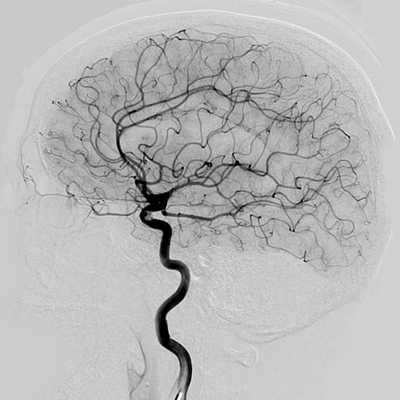

Рисунок 2. Наблюдение 2 (больной Д.). а - спиральная КТ-ангиография; б - спиральная КТ с 3D костной реконструкцией; в - МРТ; г, д - внешний вид больного до и после операции.

При МРТ головного мозга в мягких тканях головы (см. рис. 2, а) выявляется образование, состоящее из двух частей - 30×48 и 40×17 мм. На спиральных компьютерных ангиограммах (см. рис. 2, б) определяется экстракраниальное образование в задних отделах лобной области и медиальных отделах обеих теменных областей, состоящее из двух частей размером 30×48 и 40×17 мм, вызывающих атрофию от давления обеих теменных костей (костный дефект чешуи лобной кости (см. рис. 2, в) в области большого родничка размером 128×25 мм), дренирующееся из передней камеры в среднюю треть верхнего сагиттального синуса; приводящих артериальных сосудов не выявлено. Больному было проведено двухэтапное микрохирургическое вмешательство. В послеоперационном периоде признаков венозной гипертензии не отмечалось, очаговая симптоматика не выявлена, косметический дефект отсутствует (см. рис. 2, д).

В случае пациента Д. проведения МРТ и спиральной компьютерной ангиографии головного мозга явилось достаточным для установления диагноза. В случае пациента М. данные спиральной КТ неубедительно указывали на отсутствие артериовенозного шунтирования.